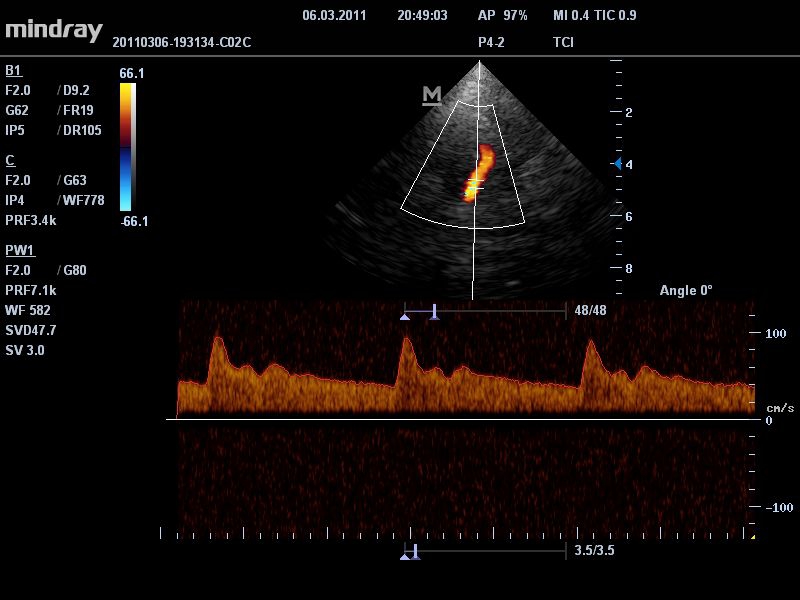

Импульсно-волновой допплер:

Да

Цветовой допплер:

• Режимы сканирования: B/M/CFM/PDI/Направленный PDI/PW, HPRF, Тканевая гармоника, М- и цветной М-режим.